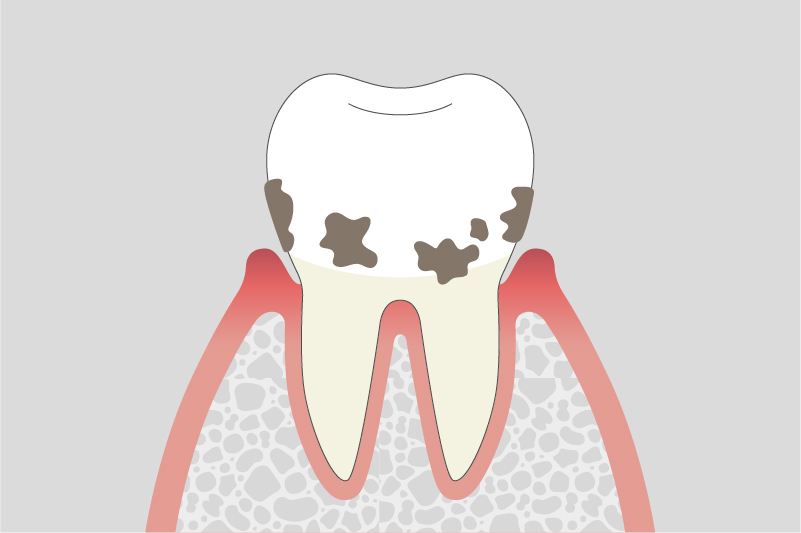

軽度歯周炎

歯周ポケットが深くなり、歯ぐきの腫れが続く。

中等度歯周炎

歯を支える骨が溶け始め、歯がグラつくことがある。